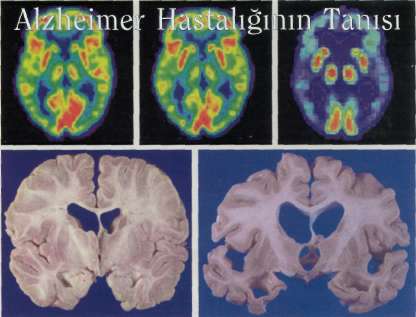

Alzheimer hastalığı, beyinde işlevsel ve yapısal değişikliklere neden olur. Üst sırada, 20 yaşındaki

(solda) ve 80 yaşındaki (ortada) sağlıklı bireylerin ve bir Alzheimer hastasının (sağda) beyinlerindeki

kan basıncı değişimlerinin ölçüldüğü PET taramaları görülüyor. Tarama sırasında, hastalıklı beyindeki

kan basıncı değişimlerinin azlığı, bilişsel işlevlerin azaldığına işaret ediyor. Alt sıradaysa, normal (solda)

ve ilerlemiş bir Alzheimerlı beynin (sağda) yapısal farklılıkları görülüyor.

Günümüzde Alzheimer tanısı koymak için, sağlıklı vücut dokularına zarar vermeyen fonksiyonel görüntüleme tekniklerinin yanısıra, davranış değerlendirme ölçeğinden yararlanılıyor. Bu ölçekte, bir düzine kadar farklı bilişsel parametre var. Bu parmetrelerin tümü, bir tanı konulmadan önce önemli değişiklikler göstermek zorunda. Beyin etkinliklerini doğrudan inceleyen iki yöntem, günümüzde Alzheimer hastalığıyla bağlantılı yapısal ve işlevsel değişiklikleri belgelemede oldukça değerli araçlar. Bunlardan ilki Man-

yetik Rezonans Görüntüleme (MRI), beynin to-pografisinin detaylı bir üç boyutlu resmini sağlıyor. Bu teknikle, hastalığın ilerlemesiyle oluşan beyin dokusu kayıpları görülebiliyor. Hastalık henüz erken evredeyken, henüz bilişsel bozukluklar davranışsal tanıya izin vermezken, beyin hacminde azalma farkedilebiliyor. Fonksiyonel MRI (fMRI) ve pozitron emisyon tomografi (PET), beyindeki etkin bölgeleri çözmede oldukça yaygın kullanılan iki yötem. Bu yöntemler, beynin belli bölgeleri hasar gördüğünde ortaya çıkan zihinsel bozuklukları tanımlamada çok önemliler. Bu yöntemlerle yapılan beyin taramaları sırasında kişiler çeşitli bilişsel etkinliklere yoğunlaştırıyor ve beynin farklı bölgelerindeki kan basıncı değişimleri ölçülüyor. Alzheimer'lı kişilerin beyin görüntüleriyle, normal kişilerin beyin taramaları arasında dramatik farklılıklar olabiliyor. Bu araçları kullanarak yapılabilen erken tanı çok önemli, etkin bir tedavi olası olduğundaysa daha da önem kazanacaklar.